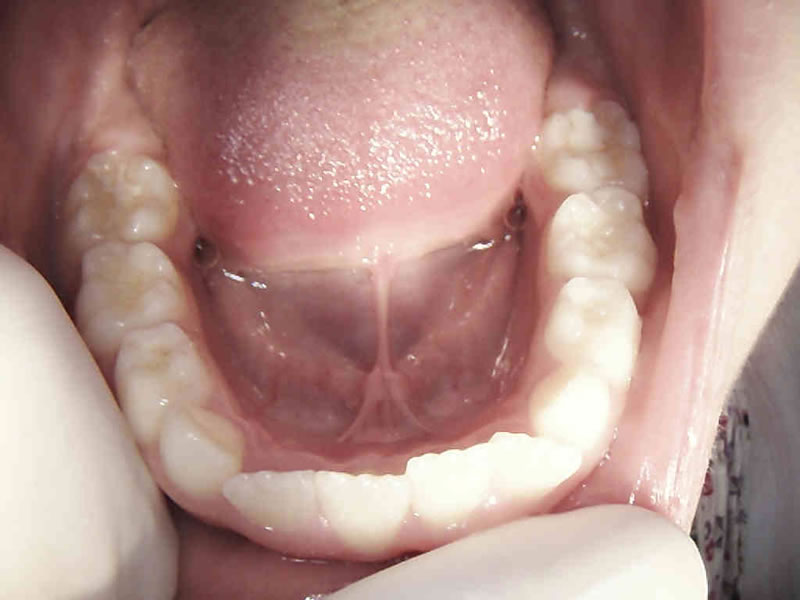

Intraoralna kamera

Prikaz zuba intraoralnom kamerom pod povećanjem i do 60 puta omogućuje nam uvid u stanje svakog pojedinog zuba i precizno planiranje radova. Jednako tako važna je i mogućnost jasnog prikaza zubnih lukova u cjelini i prikaza plana terapije našim pacijentima.